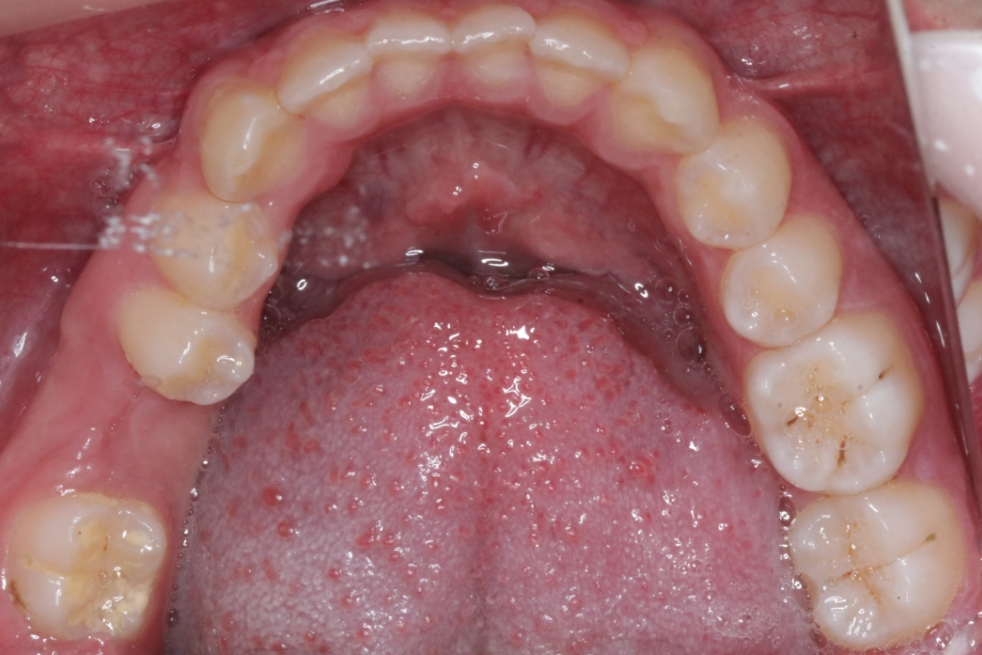

治疗前                        治疗后

无托槽隐形矫治技术

儿童错合畸形早期矫治是阻断影响儿童颌骨、牙齿正常发育的因素,促进颌面部正常发育,降低II期矫正的难度,减少II期矫正的时间,甚至不需要II期矫正。让孩子早期获得自信,绽放灿烂笑容。

术前→术后